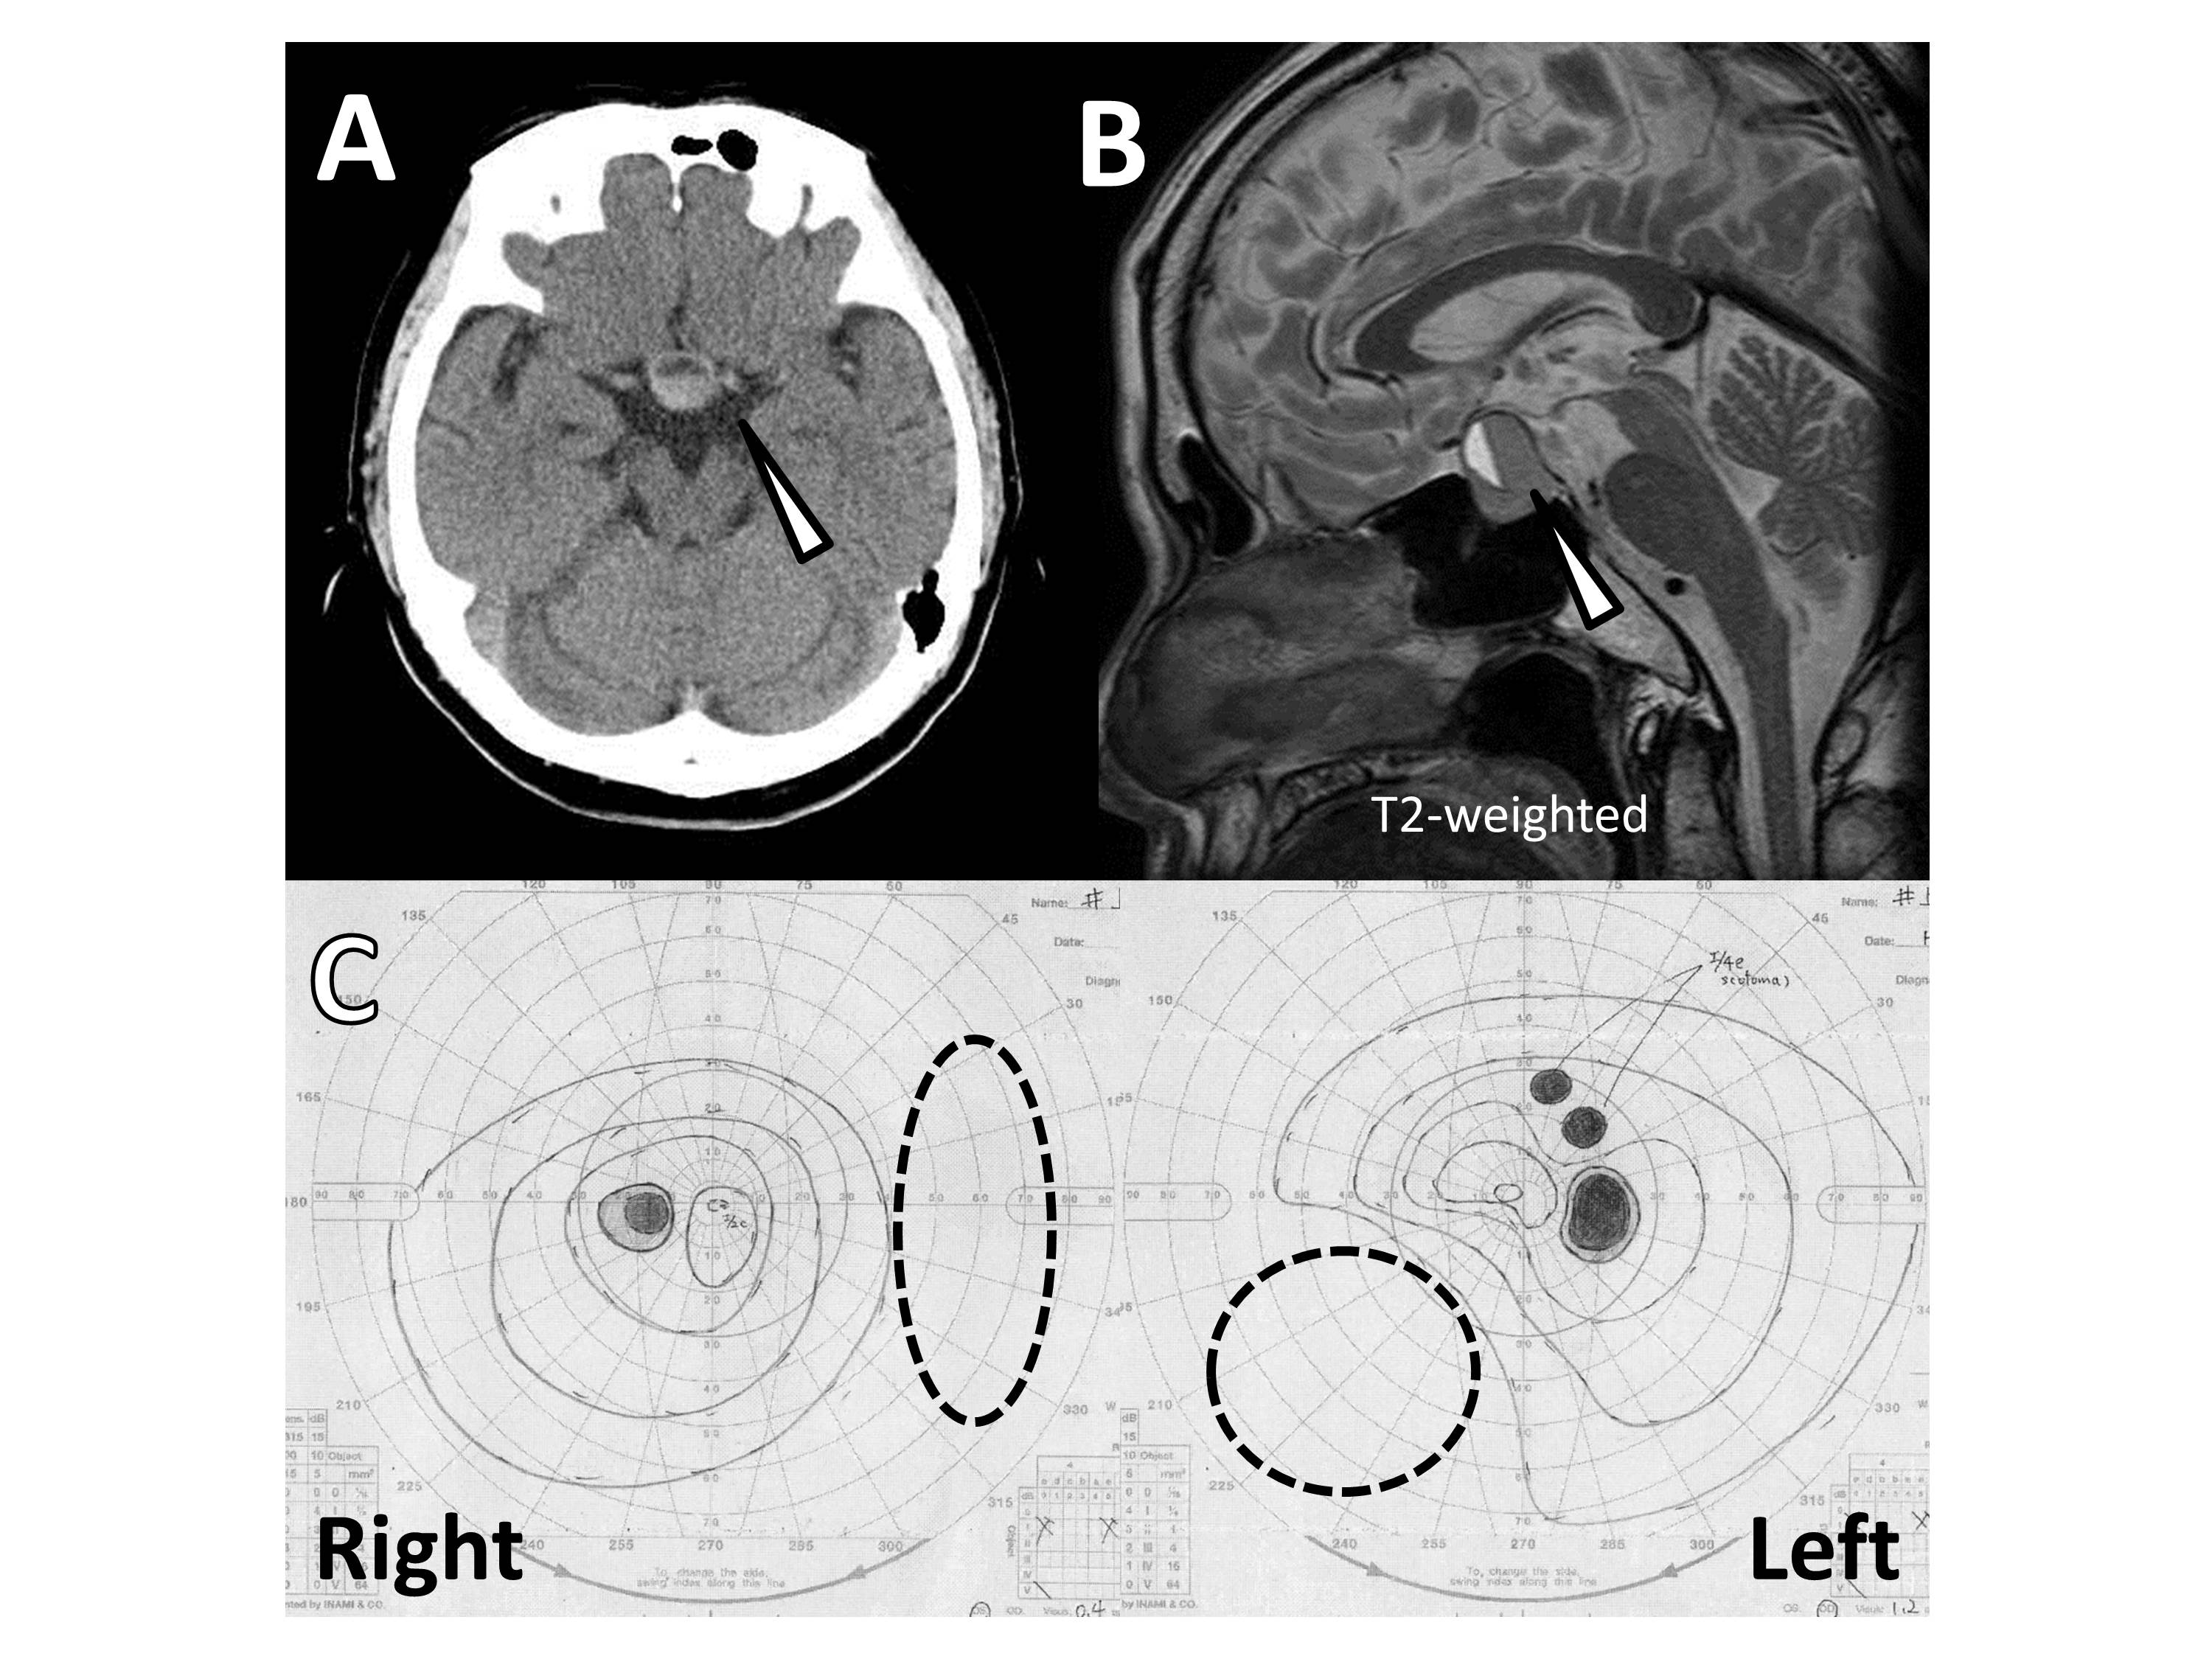

Case Presentation: A 67-year-old Japanese man was brought to our hospital because of a headache. He had noticed his headache and retroorbital pain four days before and they had been getting worse gradually. Subsequently, he noticed double vision and left drooping eyelid in the morning of the day before his first visit. He did not have particular past medical history, medication and family history. On examination, his vital signs were normal but the confrontation visual field testing disclosed binasal visual field defect. His left upper eyelid showed blepharoptosis and a left ophthalmoplegia could be seen but the lateral rectus and oblique muscle of his left eye and right extraocular muscles are left intact. Also, his left pupil was a little dilated compared with right one. These findings suggested left oculomotor palsy. Laboratory studies were normal, including a blood glucose level and electrolytes. An emergent brain computed tomography scan revealed the high-density area and niveau formation of sella turcica (figure A). An enhanced brain magnetic resonance imaging also showed the pituitary tumor with niveau formation (figure B). Goldman perimeter test was performed and it also showed binasal visual field defect (figure C, the areas surrounded by a dashed line represented defective areas). The pituitary hormone function tests were normal. Because of a left oculomotor palsy, endoscopic transsphenoidal surgery was carried out for decompression on the 11th day of admission. The pathological examination documented a pituitary adenoma with hemorrhage, without evidence of infarction, which was consistent with the diagnosis of pituitary apoplexy. His left ptosis had been partially improved four days after the operation.